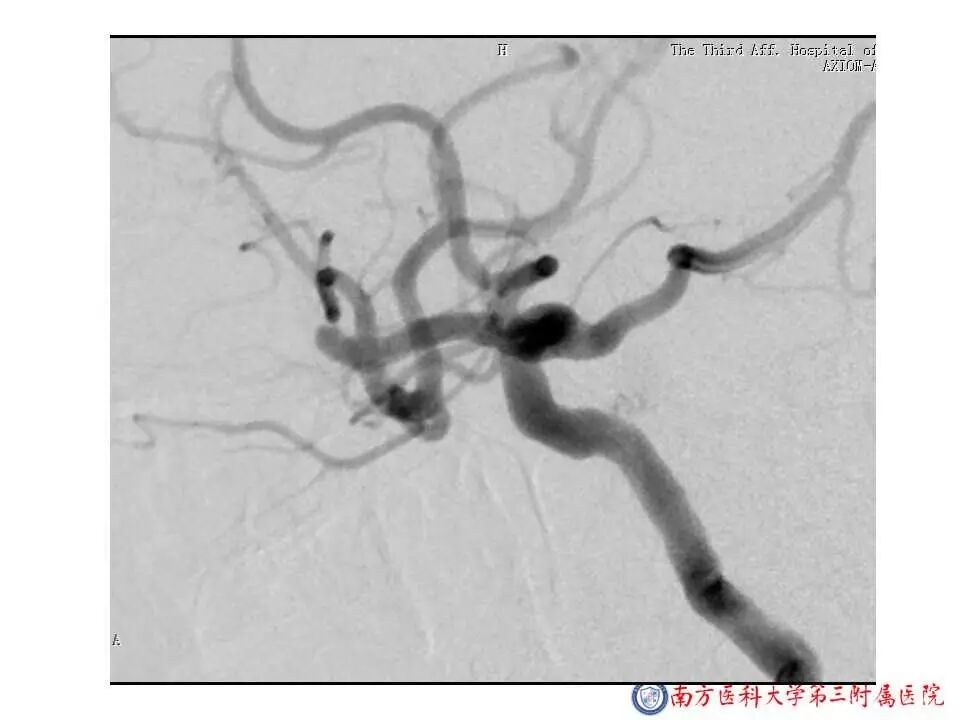

今天为大家分享的是“强生医疗CNV-神经介入专栏”第二十五期,由南方医科大学第三附属医院神经外科主任黄理金教授带来的“Enterprise支架辅助栓塞动脉瘤的优势”精彩讲课视频及PPT,欢迎观看。文章仅代表作者个人观点,如有不同见解,欢迎同道斧正!